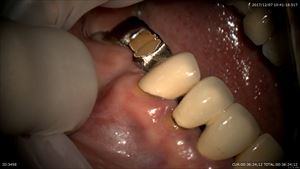

このブリッジの奥歯です。

外して

土台を外します。嫌な予感

この部分が深そう

なにがまずいかというとフェルールがとれないのと根管治療時クランプがかけられない。

そこでクラウンレングスという手法で歯茎の整形を行いクランプがかけられる様にしました。

これでクランプがかけられます。根管治療が可能に!!